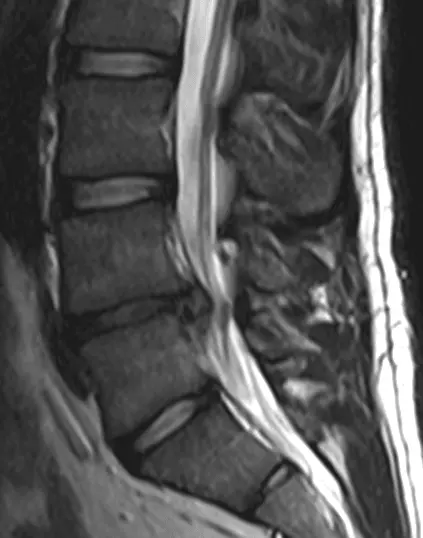

It most commonly occurs at L4/5 or L5/S1 and the most common type of herniation is a para-central prolapse, meaning that the disc prolapse is off-centre (96% of cases), but can be a central prolapse (2% of cases) or a lateral prolapse (2% of cases). Disc herniation commonly presents with unilateral back pain and paraesthesia that radiates into dermatomes supplied by the affected nerve roots.

MRI provides the most conclusive evidence for diagnosis of a disc herniation, with CT used if MRI is contraindicated. Plain X-rays do not show disc herniation but may be used to assess alternative causes of back pain. Treatment is pain management, physiotherapy, weight control and surgery if the case is causing severe pain.

Image - An MRI of a L4/L5 disc herniation

Creative commons source by Edave [CC BY-SA 4.0 (https://creativecommons.org/licenses/by-sa/4.0)]